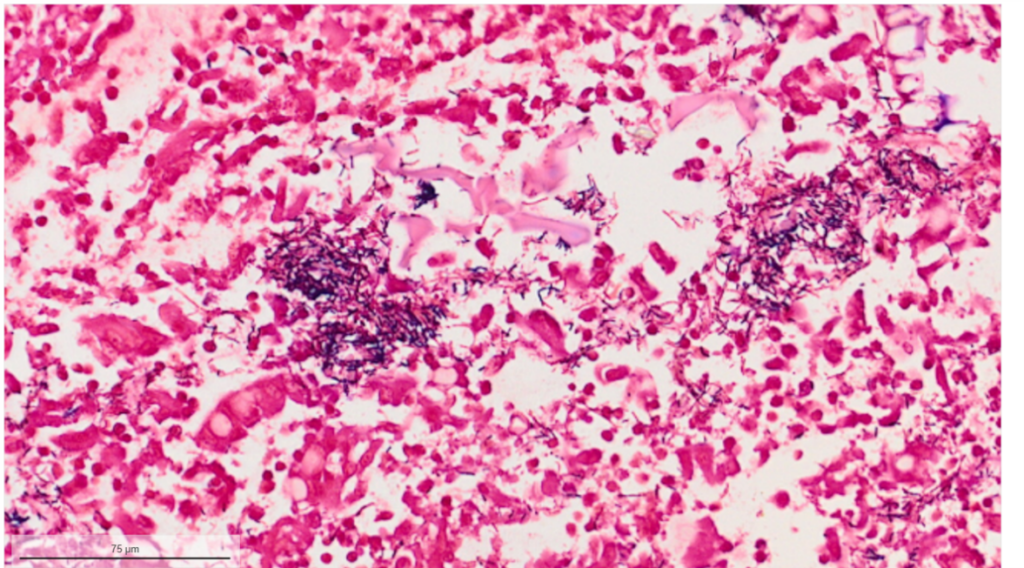

-In certain cases and upon discretion of the examining pathologists, special specific stains for suspected infectious diseases can be performed to confirm the diagnosis. Example of these stains include Gram stain (Fig.1) for bacteria, Ziehl Nelsen stain for Mycobacteria spp, Warthin starry stain for higher bacteria, Brachyspira spp and Lawsonia intracellularis (Fig.2), and immunohistochemistry for Mycoplasma spp, and selected viral diseases (e.g. PVC2, ILT and PRRS).

Fig.1 Gram stain of swine colon section reveals gram-positive bacilli (arrows) reminiscent of Clostridial spp.